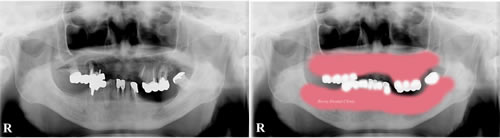

治療前

下の画像は歯を欠損して長期間放置して歯が歯並びや歯の位置が元の位置と違ってきたため噛み合わせが悪くなった症例です。

実際に歯ぐきをピンク色でイメージしてみると噛み合わせが悪くなっている事が分かります。このままの状態で入れ歯治療やインプラン治療などは人工物を適切な隙間(クリアランス)がないのでできません。